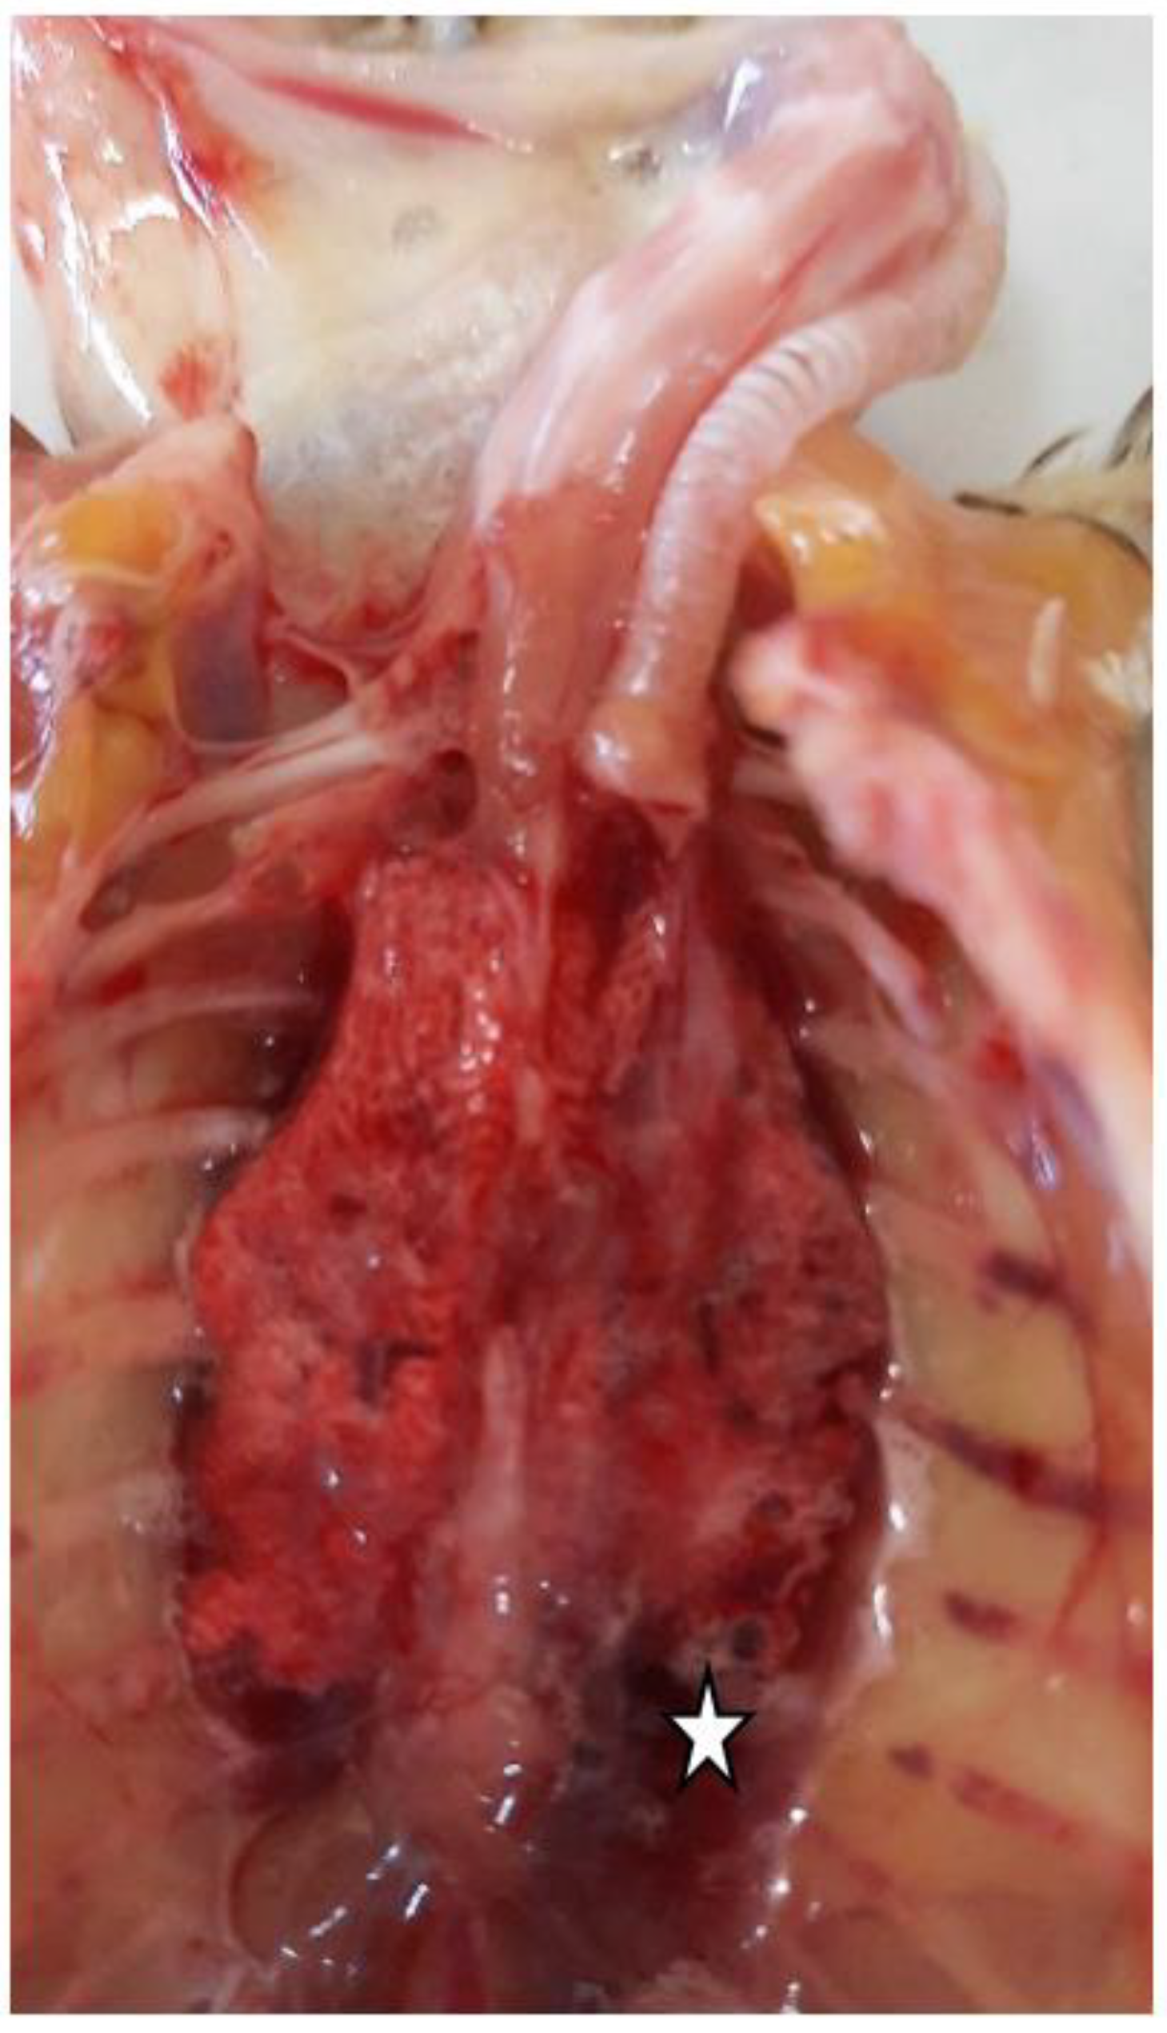

The coelomic cavity of the Caique was opened and examined. Kidneys and lungs were congested, and pulmonary edema was also present (Figure 2). Slightly enlarged and congestive liver was observed with hemorrhagic petechiae on the surface.

Figure 2.

Congestive lungs and pulmonary edema (white star) identified during the necropsy of the Caique.